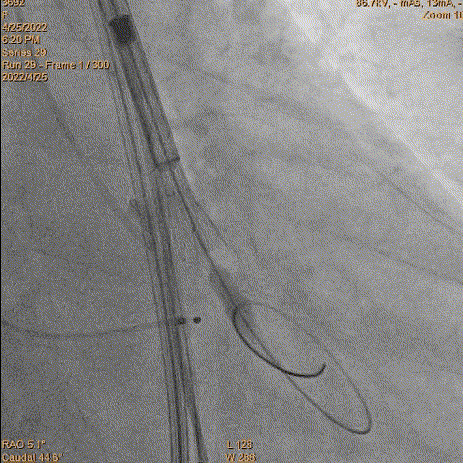

3、球囊预扩:由于钙化严重球囊无法通过,遂使用圈套器抓捕球囊。

套圈器抓球囊过瓣

20mm球囊预扩

导丝位置改变

对侧上圈套器准备

4、跨瓣:瓣膜跨瓣出现困难,计划使用圈套器。由于没有22F大鞘,内连鞘无法拆卸,选择左侧穿刺导入导管。右侧双导丝,送入Lunderquist,心室较大。扩张后,血压较稳定。经尝试无法退球囊,撤出系统。通过对侧使用抓捕器,将导丝全撤,导入AL1.0导管重新跨瓣。鉴于左侧入路有角度,使用泥鳅导丝带上导管,做圈套器。顺利抓住J型导丝,抓捕器顺利抓捕瓣膜过瓣。